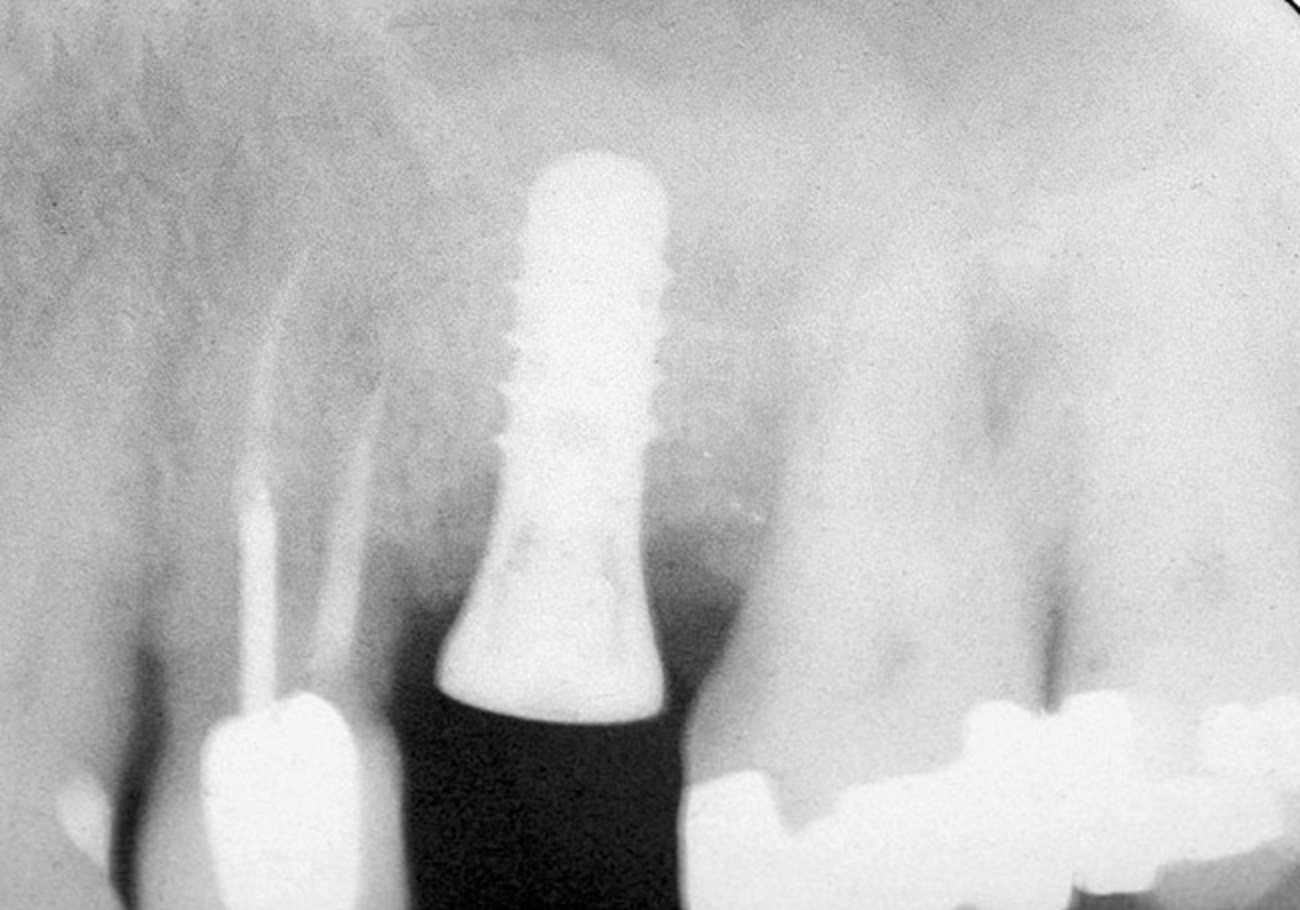

Figure 15  Implant successfully placed.

Figure 15

Figure 14  Additional bone was added via the osteotomy.

Figure 14

Figure 13  Despite initial perforation into the sinus with the 2.1-mm twist drill, the drilling sequence was continued after the drill depth was adjusted to be 1 mm short of the subantral floor. The radiograph demonstrates that after the subantral floor was up-fractured and bone was added via the osteotomy, the initial puff of bone was contained. Therefore, the procedure could continue.

Figure 13